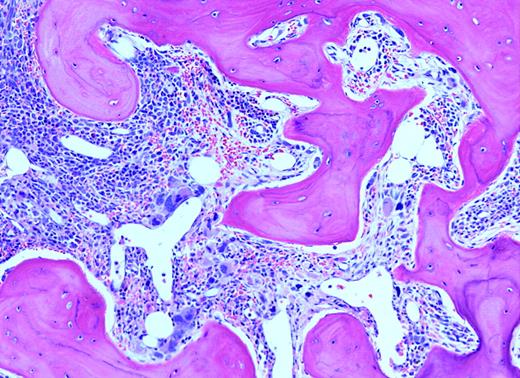

Because of the lack of precision in defining response, any codified effort evaluating therapeutic effect is to be applauded. The present effort of the advisory board of the consensus conference (ABCCs) by Barosi and colleagues is a laudable beginning. It is noted that from a standpoint of writing response guidelines, they are based upon “physicians' consensus judgement,” which is an expert opinion, not evidence based. The authors state that defining response is a complex issue, with which I agree. Their proposal basically offers a number of parameters that can be evaluated so that those interested in the treatment of this disease may readily communicate with each other, much like the tumor-node-metastasis (TNM) staging used in cancer. Yet, except for the changes in the bone marrow, many drugs will affect the white blood cell count (WBC), platelet count, hemoglobin, and spleen size without affecting marrow histologically or overall life-span. Thus, relatively minor changes will be considered “drug response” by these criteria. They correctly point out that monitoring changes in bone histology is not routine in either clinical practice or in clinical trials. This is true even in recent publications. Simplified and reproducible scoring systems for fibrosis are much needed. Whatever restores normal marrow histology is the sina qua non of therapy. I am impressed by the basic requirement of a “representative biopsy” defined as artifact free and at least 1.5 cm in length. This will require not only improvement in our hematopathology laboratories, but will also require tempered steel biopsy needles and a hematologist with a mighty arm. Likewise, many aspirations, even in early-stage disease, yield dry taps, making marrow cytogenetic analysis impossible. Perhaps one or another peripheral blood fluorescent in-situ hybridization (FISH) test for more common cytogenetic abnormalities can be considered.FIG2